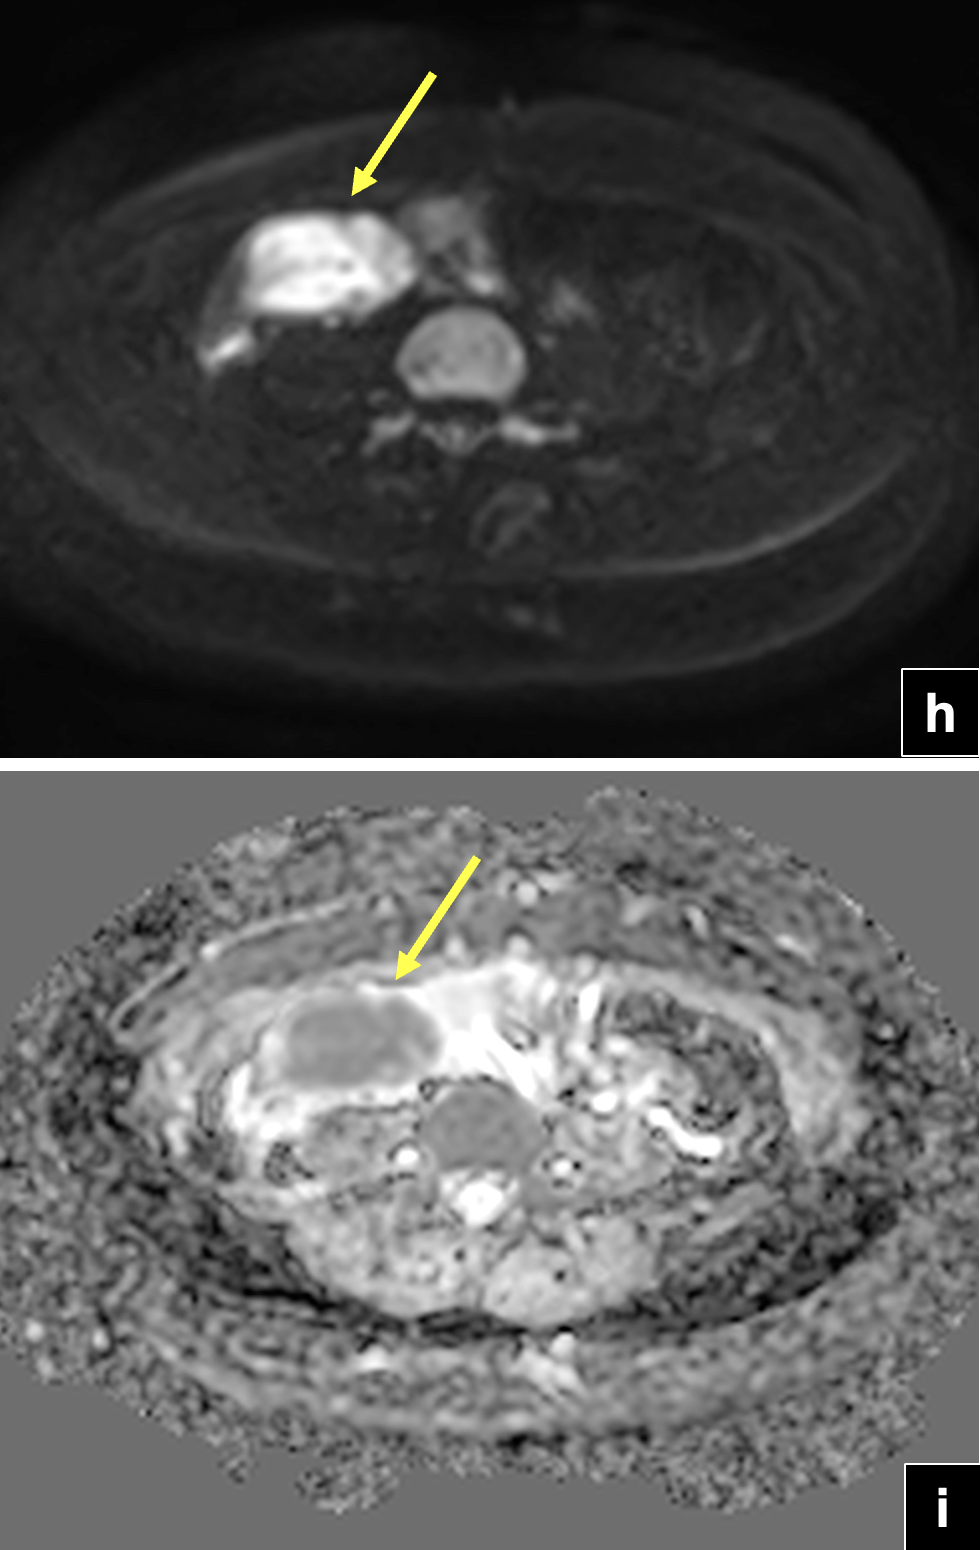

RM de abdomen y pelvis: (f) Secuencias T2 sagital. Se observa tumor solido de íleon distal (flecha) con componente quístico tabicado en hipogastrio (cabeza de flecha). Se visualiza ovario derecho de morfología conservada (asterisco). (g) Secuencia T1 FSE con Gadolinio en plano coronal. Masa quística hipogástrica con tabiques e imagen nodular periférica que realza con el uso de contraste (flecha). Efecto de masa intrabdominal visualizado por el desplazamiento hacia inferior de la pared vesical.Secuencias de pelvis axial en difusión (h,j) y mapa ADC (i,k), que demuestra restricción a la difusión de protones del componente solido del tumor de íleon en estudio y del componente sólido periférico de la masa quística hipogástrica (flecha y cabeza de flecha).